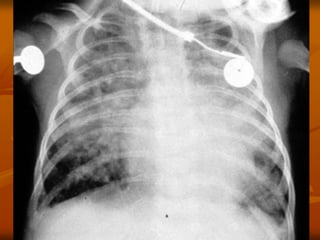

3. X QUANG PHỔI

Có thể BT: 13 % trẻ NV có XQ BT

 DH thường gặp:

 Ứ khí phế nang

 Thâm nhiễm mô kẽ, quanh PQ, PN

 Xẹp phổi: thùy trên phải

 Đông đặc phổi: 24%

 DH hiếm gặp: Tràn khí MP-TK trung thất (1%)

Tràn dịch MP

3. X QUANGPHỔI  Không đặc hiệu: Có thể BT: 13 % trẻ NV có XQ BT  DH thường gặp:  Ứ khí phế nang  Thâm nhiễm mô kẽ, quanh PQ, PN  Xẹp phổi: thùy trên phải  Đông đặc phổi: 24%  DH hiếm gặp: Tràn khí MP-TK trung thất (1%) Tràn dịch MP